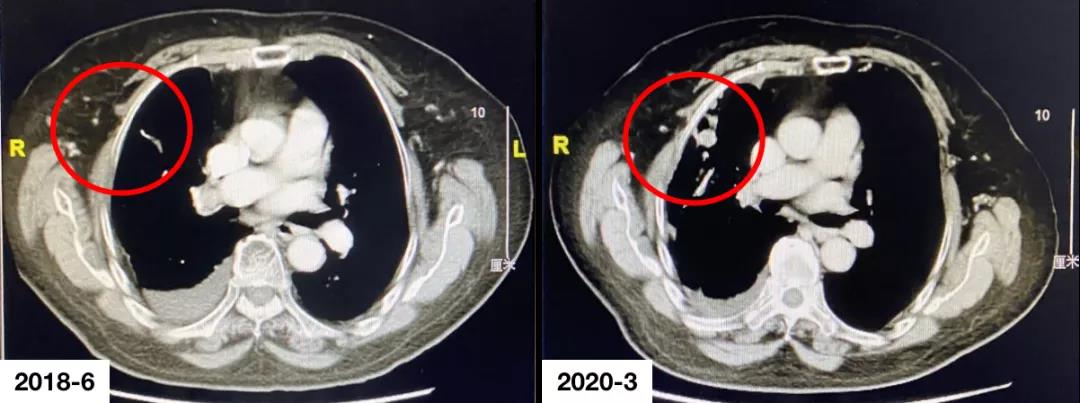

经患者充分知情同意并签署知情同意书后,考虑予以靶向联合化疗治疗。于2018年4月至2018年7月行“贝伐珠单抗+培美曲塞+卡铂”治疗4周期,右侧胸膜、右肺结节较前趋退缩,胸腔积液较前减少改善。于2018年7月至2020年1月行“贝伐珠单抗+培美曲塞”维持治疗16周期,疗效评价SD。2020年3月复查胸部CT提示:右侧胸膜、叶间胸膜、右肺多发转移灶较前明显,疗效评价:PD。

疗效评价:PD。

本例患者为右肺腺癌(TNM分期,IV期),伴右侧胸膜、叶间胸膜及右肺多发转移,驱动基因阴性。一线予以靶向联合化疗,疗效维持在SD,维持治疗16周期后复查提示病情进展。二线考虑予以免疫联合化疗,予以患者替雷利珠单抗联合多西他赛治疗2周期后,疗效即达PR,不良反应可控,患者生活质量高,二线PFS已超过5个月,且正不断延长中。